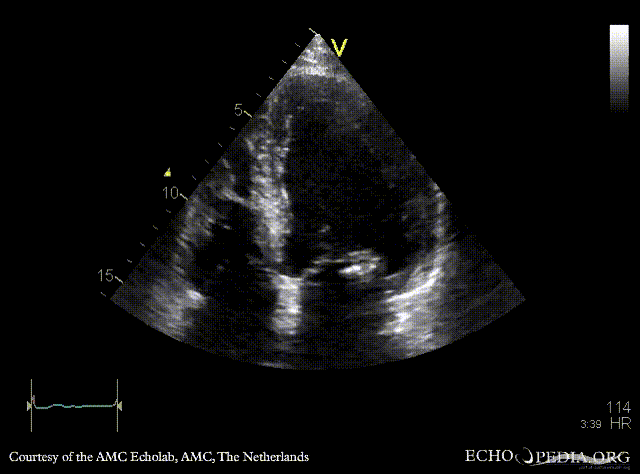

| PLAX: vegetations on PMVL | A4CH |